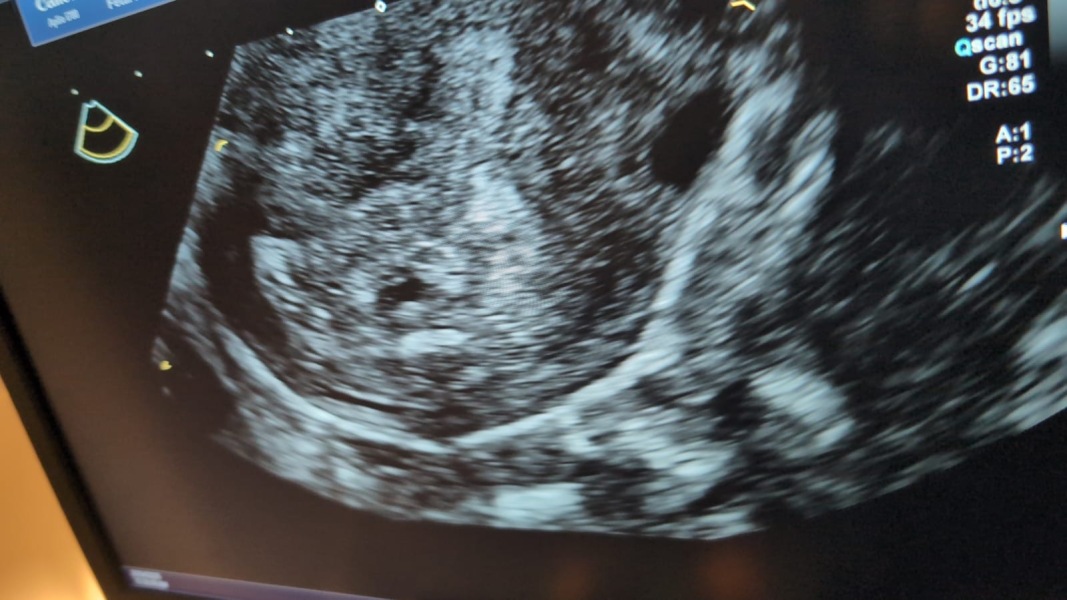

Thank you, I think the consultant will probably scan me at some point next week to confirm the miscarriage (that’s what usually happens) would be lovely to have some sort of miracle though. Just hoping it isn’t ectopic.. they saw what they thought was the start of a sac though so I’m hoping that’s unlikely.. I really don’t want the laparoscopy surgery again. I’ll attach a pic if I can x

4th missed miscarriage?

It's hard isn't it. One thing I will say, not that I want to give you false home is that I have read that HCG doubling can take three days rather than two sometimes and its obvious what they can see on the scan so I am absolutely keeping my fingers crossed that this works out well for you x